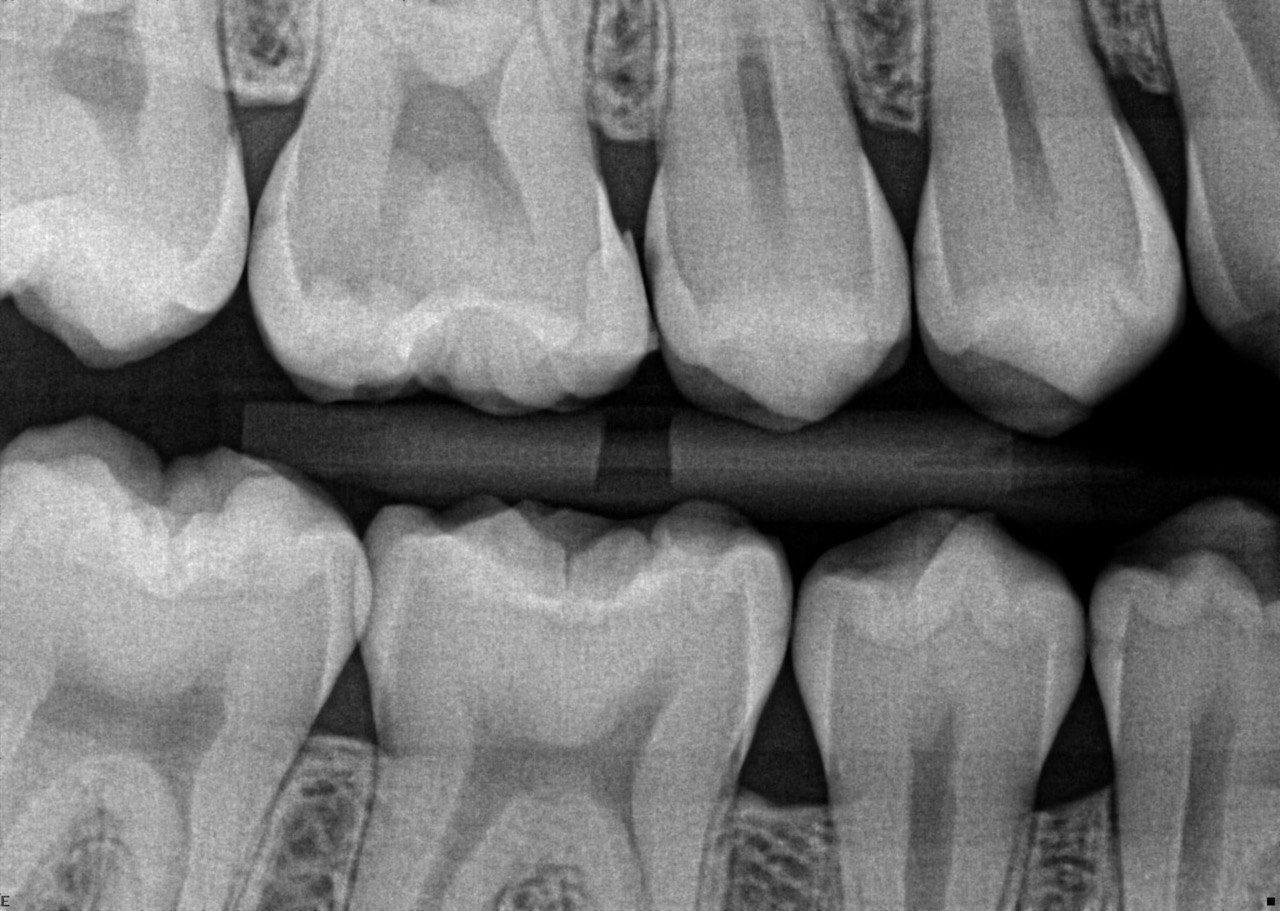

41. What options can be selected for the following X ray?

42. What is the caries on mesial surface of the tooth # 3.6?

43. Which surfaces require restoration?